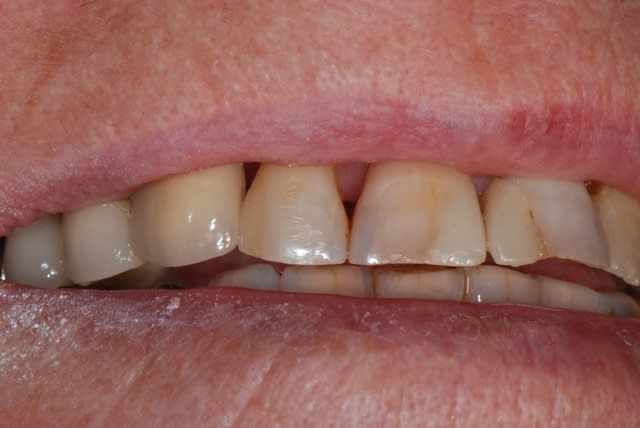

je te propose ce cas que j'ai achevé il y a 2 mois; tu verras que la notion de limite est variable, sauf celle du blocage primaire, d'où cette proposition de mise en esthétique uniquement avec un bon blocage primaire;

dans le cas présenté, je n'ai bien évidemment pas fait de mise en esthétique, j'ai simplement mis une PAP d'une dent, puisque la 14 est une CCM où je ne pouvais pas faire de collage

j'ai mis du ß TCP sans membrane, j'ai eu une très légère récession gingivale que l'utilisation des TBR Zircone autorise sans soucis avec un sourire non gingival

Sourire dqz88s - Eugenol